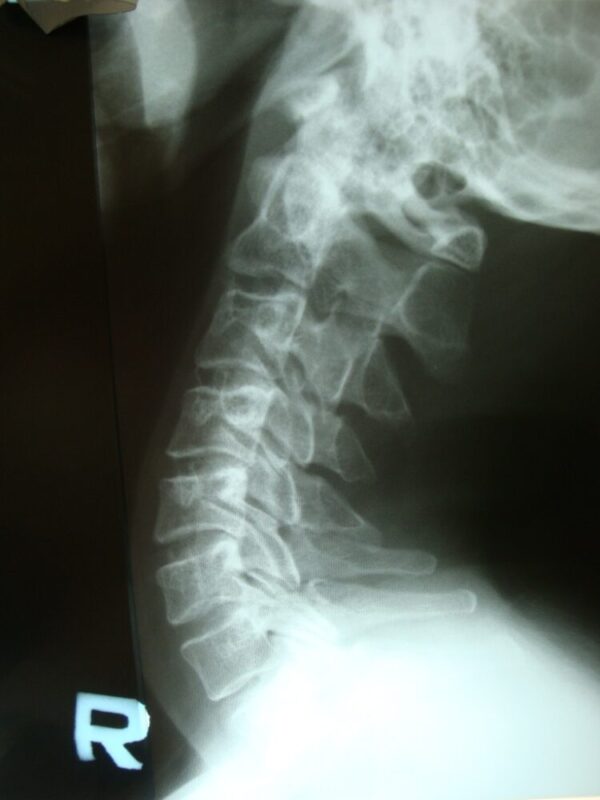

ストレートネックとは、レントゲン上、脊柱から頸椎の配列が直線状になる事(頚椎の生理的前彎の消失)を示します。